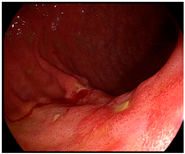

The extent of resection was determined according to the tumor location identified using the fluorescence signal from the ICG diffusion area on the gastric wall (Figure 2). As we injected ICG around the tumor before surgery, we hypothesized that the lesion was located at the center of the range of the fluorescence signal. Therefore, we decided on the gastric transection line considering the tumor location using real-time fluorescence imaging and resected the stomach proximal to the fluorescent area whenever possible. As for reconstruction methods, gastroduodenostomy, loop gastrojejunostomy, or Roux-en-Y gastrojejunostomy was considered for subtotal gastrectomy patients. Proximal gastrectomy and total gastrectomy were followed by double tract reconstruction and Roux-en-Y esophagojejunostomy. All procedures, including resection and reconstruction, were performed intracorporeally using an articulating linear stapler.

Figure 2.

(a) ICG diffusion range on a gastric wall, pinpoint mode: fluorescence signal in green overlayed on the white light image-helpful to check the fluorescence image in real-time during surgery; (b) ICG diffusion range on a gastric wall, colorized mode: fluorescence with color gradient by signal intensity overlayed on the gray-scale white light image-helpful to check the difference in fluorescence signal intensity; (c) resection of the stomach with secured proximal resection margin performed by including the entire portion of ICG diffusion range in the resected specimen.